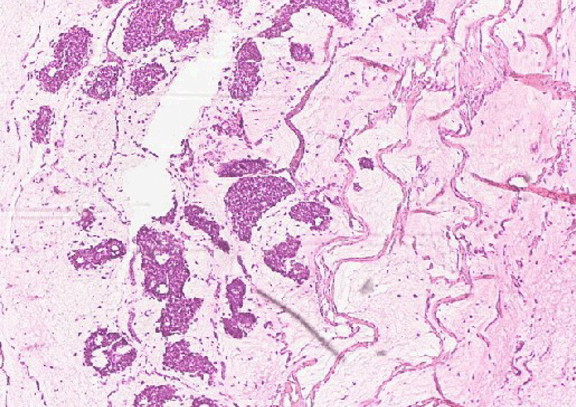

A 53-year-old female was presented to the breast clinic with a palpable breast lump. Clinically, the lump was suspicious of breast cancer. Mammogram and ultrasound scan also confirmed the suspicious nature of the lump. A free hand needle core biopsy was carried out in the one-stop triple assessment clinic on index presentation. The core biopsy material retrieved had a distinctive gross appearance, with soft, gelatinous consistency and a glistening clear almost see-through surface. (Figure 1) On this typical macroscopic appearance, a diagnosis of ‘mucinous breast carcinoma’ was made, which was subsequently confirmed on microscopic histological examination. The hallmark of mucinous carcinoma is extracellular mucin production, the extent of which varies from tumor to tumor. Typically, mucinous cancer cells in small clusters, sheets, or papillary configurations are dispersed within pools of extracellular mucin. (Figure 2)

Figure 2: Histological appearance of mucinous breast carcinoma; lakes of lightly staining mucin with islands of neoplastic cells floating (H&E stain, x200).